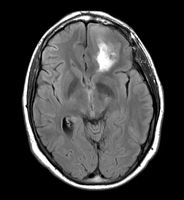

• inner part of the tumor segmented from SPGR

• outer part of the tumor segmented from post-Gad

• WM and GM segmented from N4-processed SPGR (WM segmentation of the original SPGR volume is included, note under-segmented WM in the skull base)

• all segmentations were done using FastMarching, fiducials are included for each of the segmentations

• no fine-tuning of the fiducial locations was done -- this is an example result one can get almost right away

• rule of thumb in placing fiducials: try to cover uniformly the volume you are trying to segment; this is particularly important for large structures like WM/GM